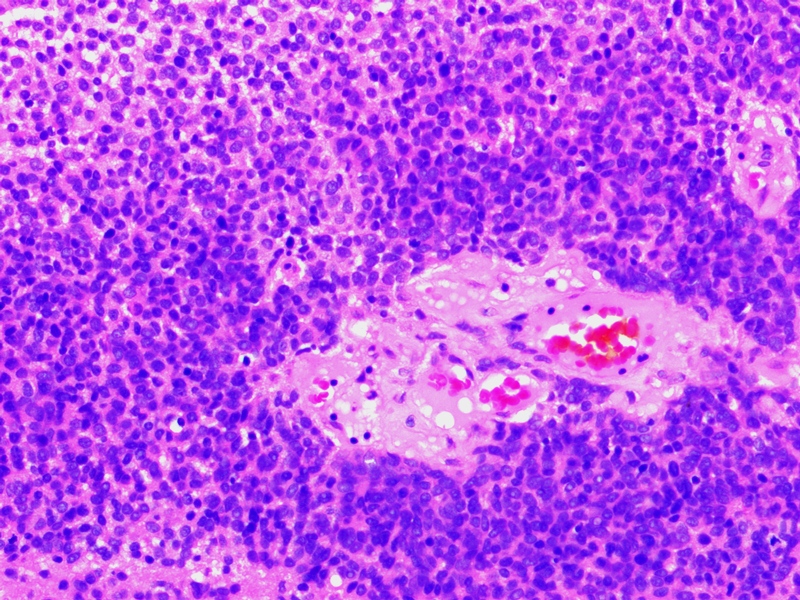

Photomicrograph shows tumour cells in sheets with round hyperchromatic nuclei and moderate amount of eosinophilic cytoplasm. (H&E, x200);

A 65-year-old post-menopausal female with no medical comorbidities (diabetes/hypertension), presented to the Emergency Department with complaints of altered sensorium, preceded by generalized malaise and sweating for 2 hours. There was no history of chest pain, headache, respiratory distress, prior fainting episodes and trauma. On examination, she was cold and clammy with pulse rate of 130 per minute, blood pressure of 90/60mm of mercury in supine position and respiratory rate of 22/minute. Her pupils were normally reacting to light. There was no pallor and cyanosis. On systemic examination, she had an irregular large lump about 15x18 cm in size located in the hypogastruim, firm in consistency, non-tender with restricted mobility. She had a GCS score of 10/15, cranial nerve examination were normal. Her reflexes were sluggish with a normal plantar reflex. Her haematological investigations and serum biochemistry including liver and renal function tests and electrocardiogram were normal except for the presence of blood glucose levels of 23mg /dl. She was given 200ml of 25% dextrose following which she regained consciousness and sugar levels returned to normal. Her hypoglycaemia was intractable and repeatedly 25% glucose had to be administered to maintain euglycaemia. Her troponin, thyroid profile, cortisol, prolactin levels were normal. Contrast Inhanced Computed Tomography (CECT) abdomen showed a multi-lobulated heterogeneous abdomino-pelvic mass with areas of necrosis and calcifications [Table/Fig-1]. Right ureter was encased by the mass with evidence of mild hydronephrosis on the same side. The uterus was displaced superiorly by the mass and cervix was not visualized separately [Table/Fig-2]. There was no metastasis or any other space occupying lesion in the abdomen. CECT Brain did not show any evidence of stroke or space occupying lesion. USG guided biopsy was done which was consistent with the diagnosis of GIST (CD 34 positive, CD117 negative) [Table/Fig-3,4 and 5]. To delineate the cause of intractable hypoglycaemia, serum insulin was done which was 4mU/L, (normal 6-25) and C-peptide was 0.3nmol/L (normal 0.33-1.0). Serum proinsulin levels were 56.4 (normal < 18.8pmol/l). IGF levels could not be done due to laboratory limitations. Due to suppressed insulin levels and raised proinsulin levels, the diagnosis of IGF-II dependent Non-islet Cell Tumour induced Hypoglycaemia (NICTH), was considered. Due to poor general condition and inoperability of the tumour, Methylprednisolone was started and she was gradually weaned off from Dextrose infusions. Right ureter was stented. When she became stable, she was started on Imatinib 400 mg/day to which her symptoms and hypoglycaemic episodes responded.